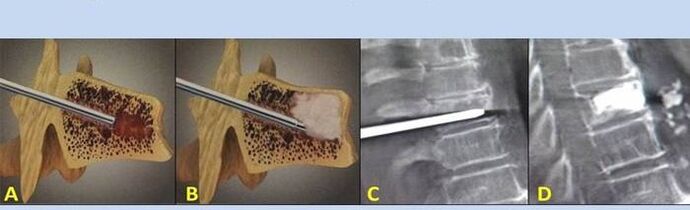

- Nucleoplasty– removal of the nucleus of the intervertebral disc.The operation relieves pressure on nerve endings.

- Puncture vertebroplasty– method of stabilizing the vertebrae.During the procedure, the doctor fills the cavities in the spine with bone cement.